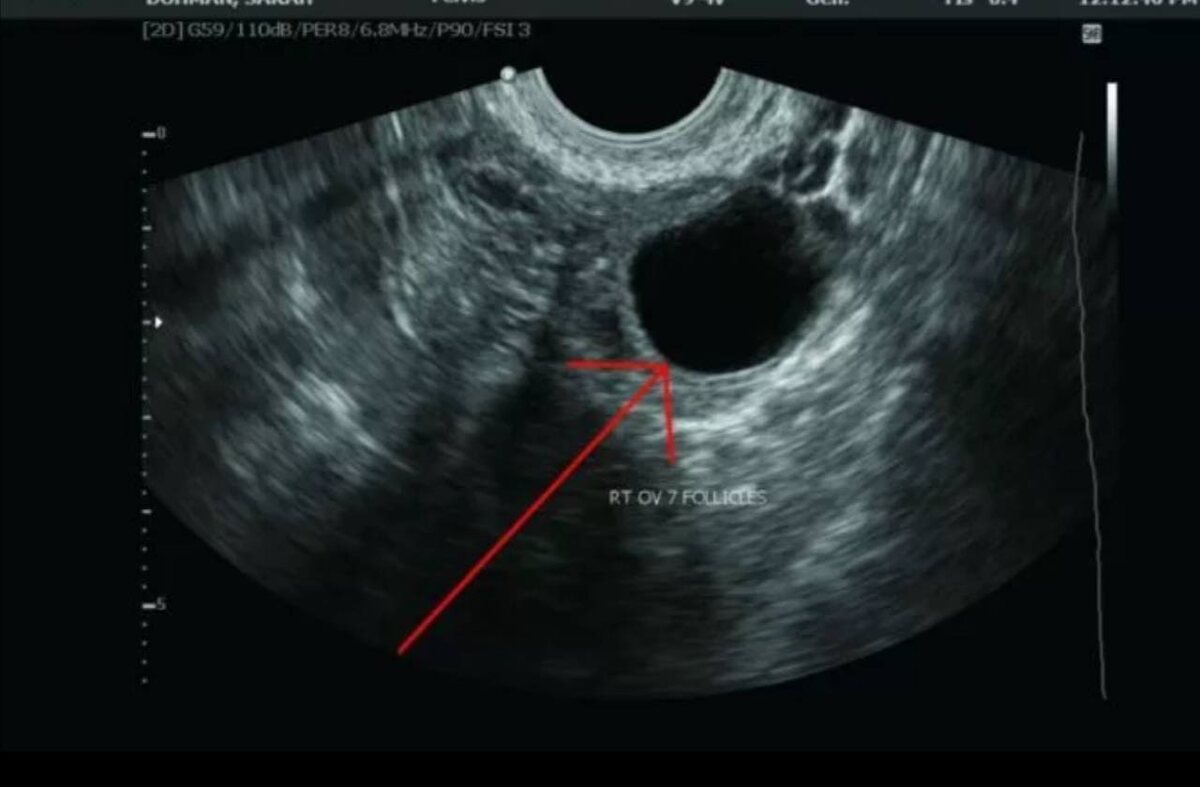

📍Фолликулометрия.

При цикле 28-30 дней на 10-11 день цикла выполняется УЗИ для определения доминантного фолликула (более 10 мм в диаметре ) и далее контролируем каждые 2 дня до овуляции. Далее по узи за 7 дней (19-21 день цикла при его продолжительности 28-30 дней )до предполагаемой менструации надо оценить наличие желтого тела .